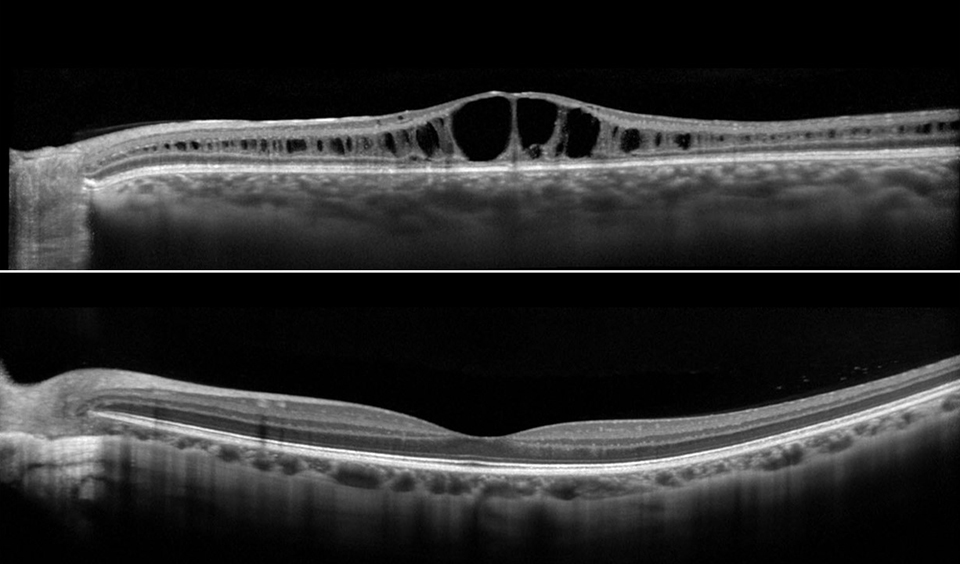

Genes Free FullText A Carrier Female Manifesting an Unusual X